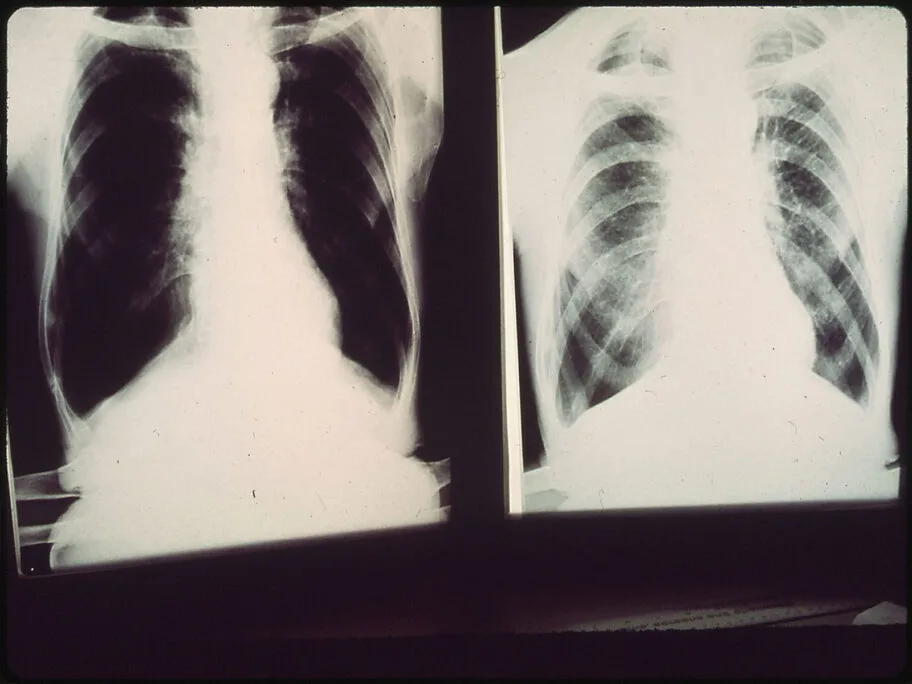

Milićeva grupa i „Koalicija za Niš“ traže da se u Knez Selu izgradi Institut za plućne bolesti

Vreme je da Niš dobije Institut za plućne bolesti – poručuju iz Grupe građana “Dr Dragan Milić” i “Koalicije za Niš” i saopštavaju da pokreću inicijativu za izgradnju ovog Instituta u Knez Selu, gde je do pre 7 godina radila Klinika za plućne bolesti. Klinika za plućne bolesti i plućna onkologija izmeštene su 2018. godine iz […]